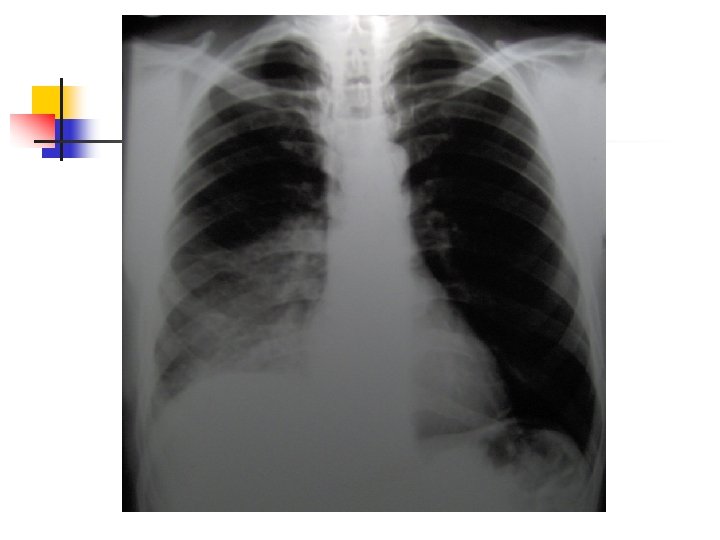

Aproximación diagnóstica: Radiología n n n 250 ml son necesarios para provocar alteraciones radiológicas. Primer signo: Borramiento del SCD Damoisseau. Desviación de estructuras. Derrame tabicado.